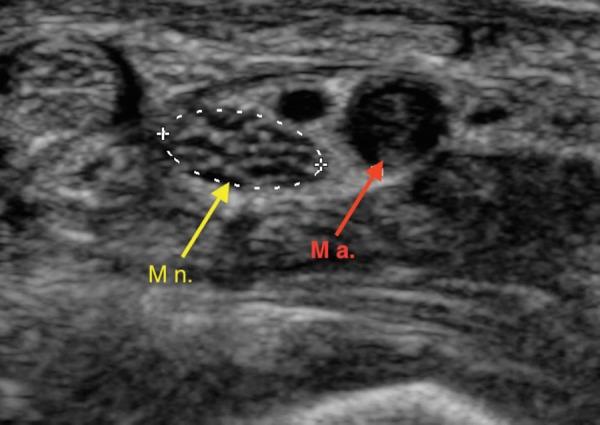

: Carpal tunnel syndrome (CTS) is a sporadic event with compression of the median nerve (MN). Persistent median artery (PMA) thrombosis is an exceptionally rare cause of CTS. : 38-year-old male presented with acute on subacute right wrist pain with positive Tinel's sign. An ultrasound and computed angiography study confirmed a PMA with thrombosis. The patient was treated with intravenous heparin then discharged home on enoxaparin and warfarin crossover. : PMA can lead to CTS by compression from the adjacent median nerve. Thrombosis of the PMA can also lead to CTS. Surgical intervention is needed in cases of severe CTS. Carpal tunnel release is usually successful. Excision of the PMA can risk vascular compromise of the digits. Ultrasound is excellent for detecting rare causes of CTS. : Ultrasound examination for CTS should include search for PMA and associated anatomical variations.

腕管综合征(CTS)是一种因正中神经(MN)受压引起的散发性疾病。持续性正中动脉(PMA)血栓形成是CTS极为罕见的病因。一名38岁男性因亚急性右腕疼痛伴Tinel征阳性就诊。超声和计算机血管造影检查证实存在PMA伴血栓形成。患者先接受静脉肝素治疗,然后出院时改用依诺肝素和华法林交叉治疗。PMA可通过对相邻正中神经的压迫导致CTS。PMA血栓形成也可导致CTS。严重CTS病例需要手术干预。腕管松解术通常很成功。切除PMA可能会有手指血管受损的风险。超声对于检测CTS的罕见病因非常有效。对于CTS的超声检查应包括寻找PMA及相关解剖变异。